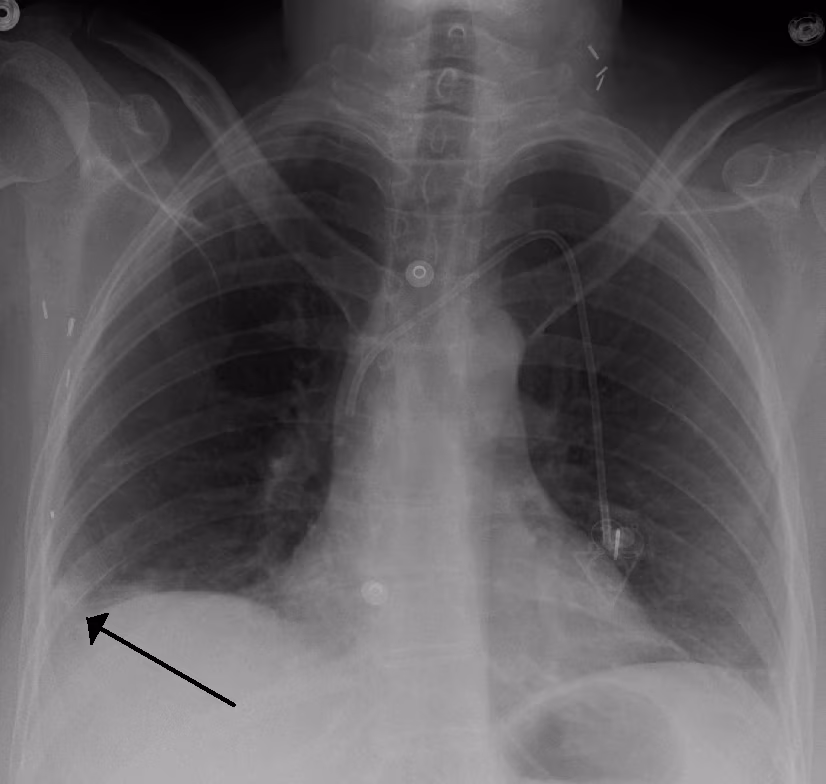

A Hampton hump in a person with a right lower lobe pulmonary embolism